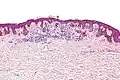

-

Low magnification

Low magnification -

Intermediate magnification

Intermediate magnification -

Very high magnification

Very high magnification